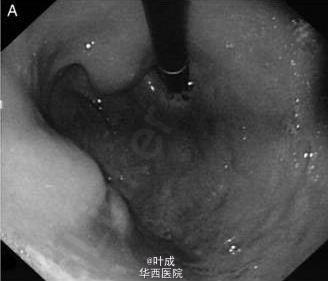

来自印度海得拉巴亚洲胃肠病研究所的 Ramchandani 等报道了一个罕见的胃结核病例,发表在最近的 Gut 杂志上。患者,男性,47 岁,消化不良、上腹部不适 2 个月,伴有体重减轻约 4kg,无消化道出血,无发热、咳嗽。既往否认传染病、手术史。体格检查无特殊。实验室检查示:血红蛋白 114g/L,血沉增快 54mm/h。心电图、胸片无异常。 胃镜示:胃体处可见多个粘膜下肿物 (图 A),贲门、胃窦粘膜正常。血中嗜铬粒蛋白 A 和尿液中 5 羟基吲哚乙酸水平正常。行超声内镜检查(图 B) 并于引导下行肿物穿刺,病理示可见肉芽肿。